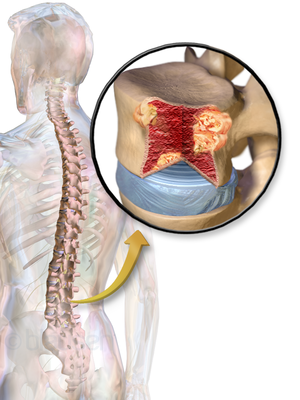

ورم نقوي متعدد

| Multiple myeloma | |

ورم نقوي متعدد إنگليزية: Multiple Myeloma هو مرض سرطاني يصيب الخلايا البلازمية من نوع B مما يؤدي إلى تكاثر هذه الخلايا بشكل غير طبيعي و تكدسها في نخاع العظم. يشكل ما نسبته 1% من الأمراض السرطانية بشكل عام و 10% من الأصابات بسرطان الدم. معدل عمر المريض عند تشخيص المرض يتراوح مابين 60-65 عاما. ينتشر المرض بين الأشخاص ذوي الأصول الإفريقية أكثر من البيض و الآسيويون.

CT scan of the lower vertebral column in a man with multiple myeloma, showing multiple osteoblastic lesions. These are more radiodense (brighter in this image) than the surrounding cancellous bone, in contrast to osteolytic lesions which are less radiodense.